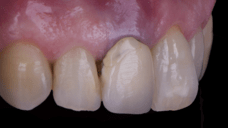

After an appropriate healing period, the definitive prosthesis was planned and delivered. A screw-retained zirconia crown was fabricated to ensure long-term durability, optimal esthetics, and retrievability. Zirconia was selected for its mechanical strength and excellent esthetic properties, blending seamlessly with the adjacent natural dentition in both form and color.

The final crown was designed to maintain the gingival architecture that had been shaped by the provisional. Special attention was paid to the emergence profile, contact points, and translucency to achieve harmony with the patient’s smile. The definitive restoration provided functional stability and esthetic integration, fulfilling the patient’s expectations for a fixed and natural solution.